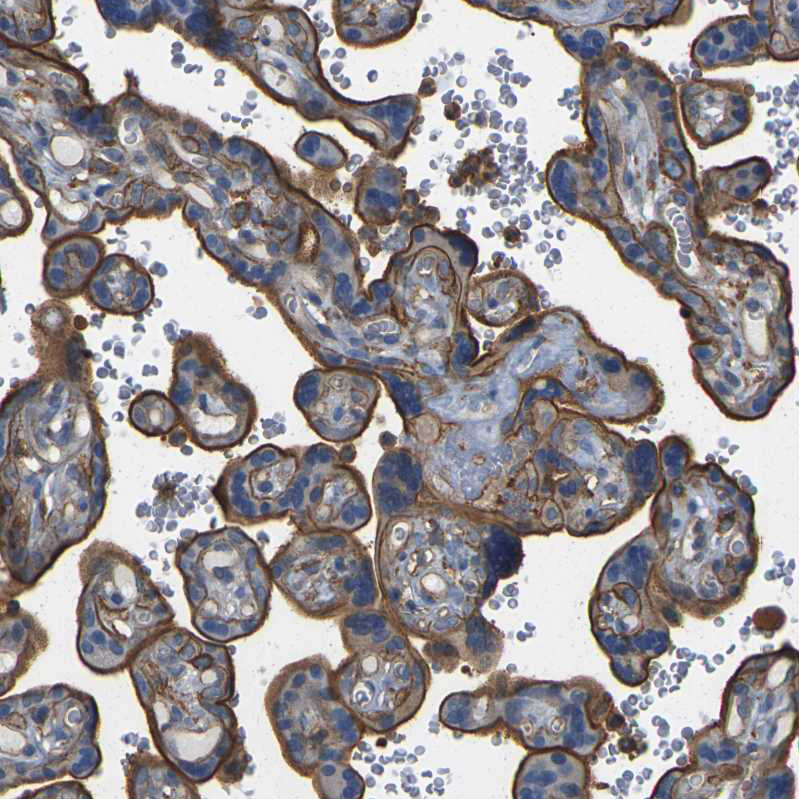

Immunohistochemistry analysis in human placenta and skeletal muscle tissues using HPA014055 antibody. Corresponding IQGAP1 RNA-seq data are presented for the same tissues.